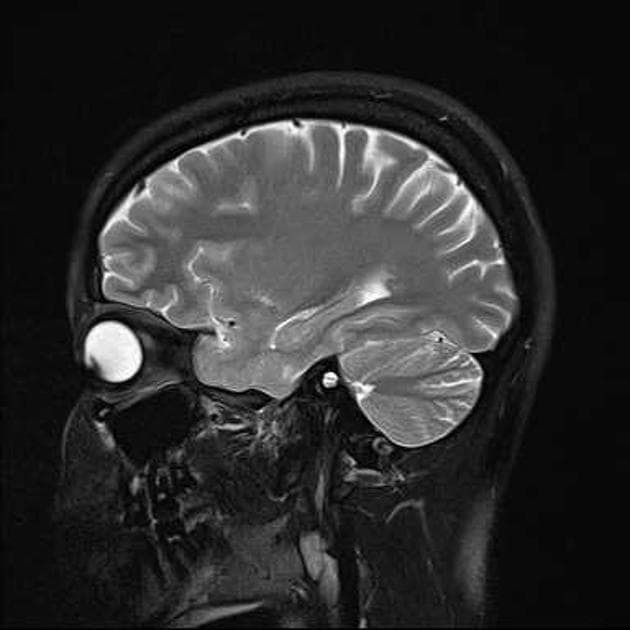

Ca bệnhU oncocytoma tế bào thoi của tuyến yên

U oncocytoma tế bào thoi của tuyến yên

- Khối u đặc vùng yên (lớn hơn 1 cm) với sự lan lên trên yên (suprasellar extension).

- Tăng quang không đồng nhất (heterogeneous hyperenhancement).

- Tuyến yên trước (adenohypophysis) và cuống tuyến yên bị đẩy lệch về phía trước.

- Giao thoa thị giác (optic chiasm) bị đẩy và cong lên trên.

- Trên hình ảnh học, trường hợp này sẽ được chẩn đoán là u tuyến yên lớn (pituitary macroadenoma) trong hơn 99,9% các trường hợp.

- U sọ hầu (craniopharyngioma) và, ở nhóm tuổi này, di căn (metastasis), có thể được xem xét trong chẩn đoán phân biệt.

- Việc tuyến yên trước và cuống tuyến bị đẩy lệch về phía trước là bất thường, nhưng có lẽ không đủ để làm thay đổi chẩn đoán sang các u tuyến yên rất hiếm gặp khác.

- Tuy nhiên, khối u này đã làm xao nhãng các bác sĩ chẩn đoán hình ảnh, dẫn đến bỏ sót phình động mạch não trước (ACom aneurysm) trên nhiều lần chụp hình.

U oncocytoma tế bào thoi của tuyến yên (Spindle cell oncocytoma of the pituitary gland)

U oncocytoma tế bào thoi là một khối u lành tính, rất hiếm gặp, bắt nguồn từ các tế bào tuyến yên trước. Bệnh thường xuất hiện ở người lớn với khối u đặc lớn, lan lên trên yên, có hình ảnh học không thể phân biệt với u tuyến yên lớn. Mặc dù được xếp vào nhóm lành tính, u vẫn có thể gây hiệu ứng khối đáng kể, dẫn đến chèn ép đường dẫn truyền thị giác và rối loạn nội tiết. Về mặt mô học, u đặc trưng bởi các tế bào hình thoi, chất bào ưa acid (oncocytic) và sắp xếp theo kiểu bó hoặc hình xoắn ốc. Các chẩn đoán phân biệt chính bao gồm u tuyến yên lớn, u sọ hầu và di căn. Trường hợp này nhấn mạnh thách thức trong chẩn đoán các khối u vùng yên hiếm gặp và cần thiết phải đánh giá hình ảnh toàn diện để tránh bỏ sót các tổn thương nguy hiểm đi kèm như phình động mạch não trước, có thể bị che khuất bởi khối u chính.